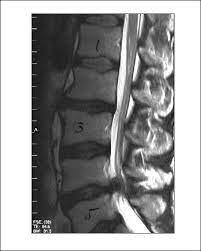

Bandscheiben op lws 4 5. Sie kommen meist zwischen den Wirbeln LWK Lendenwirbelkörper 45 und LWK 5SWK 1 Sakralwirbelkörper vor an der vorletzten und letzten Bandscheibe. Bandscheibenvorfälle sind Teil einer natürlichen Abnützung des Gewebes. Drückt der Gallertkern auf einen Rückenmarksnerven leiden Betroffene unter starken Rückenschmerzen die teilweise bis in Arme und Beine ausstrahlen.

Ursachen Diagnose und Therapie. Wie der Bandscheiben-Vorfall Prolaps ist die Bandscheiben-Vorwölbung Protrusion besonders häufig in der Etage bei L4L5 zwischen dem 4.

Wenn die Physiotherapie und Medikamente nicht mehr helfen und die Schmerzen zu stark sind oder wenn der Druck auf die Nerven Ausfälle verursacht Taubheit Muskelschwäche Lähmung sollte eine Operation in Betracht gezogen werden. Bandscheibenvorfall LWS Übungen - Hier findest du 5 effektive Übungen bei einem Bandscheibenvorfall in der Lendenwirbelsäule inkl. Es geht mir zur Zeit nicht gut mache mir auch große Sorgen wie es wird in den nächsten Tagen und Wochen mit den Schmerzen und Beschwerden. Ich wurde am 4. Frank aus München in. Probieren Sie es selbst aus. Sie kommen meist zwischen den Wirbeln LWK Lendenwirbelkörper 45 und LWK 5SWK 1 Sakralwirbelkörper vor an der vorletzten und letzten Bandscheibe. Die Bandscheiben der Wirbelsäule übt eine Art Stossdämpferfunktion aus und dient der Elastizität und der Beweglichkeit der Wirbelsäule. Lendenwirbel und dem 5.

Die Bandscheibenvorfälle an der Lendenwirbelsäule sind die häufigsten Bandscheibenvorfälle an der Wirbelsäule. In der Regel verschwinden die Schmerzen zwar nach der OP es kann aber immer sein dass sich Symptome nicht zurückbilden. Wenn die Physiotherapie und Medikamente nicht mehr helfen und die Schmerzen zu stark sind oder wenn der Druck auf die Nerven Ausfälle verursacht Taubheit Muskelschwäche Lähmung sollte eine Operation in Betracht gezogen werden. 3053 Beiträge ø047Tag Hallo vor 1 Woche hatte ich eine große Bandscheiben-OP. Wie der Bandscheiben-Vorfall Prolaps ist die Bandscheiben-Vorwölbung Protrusion besonders häufig in der Etage bei L4L5 zwischen dem 4. Bandscheibenvorfall 4-5 Lendenwirbel Hey S-A2011 danke für Deine Erzählung. Alleine in Deutschland werden jährlich ungefähr 150000 Bandscheibenvorfälle operativ behandelt.